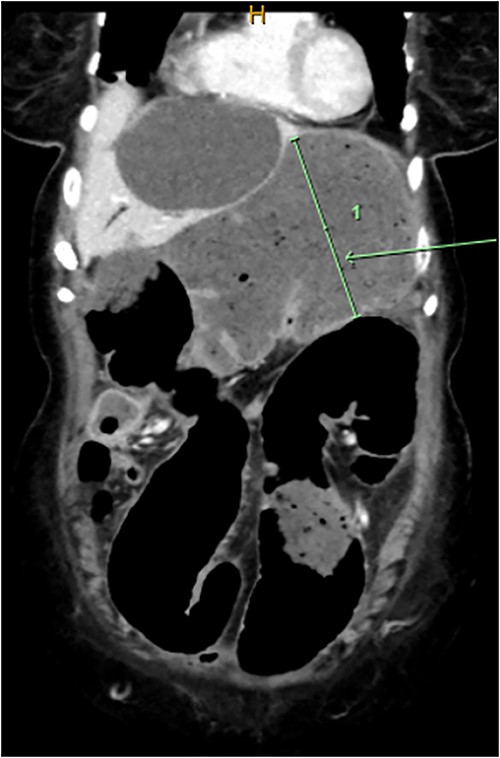

Computed tomography on current presentation demonstrated a mechanical LBO with a transition point at the anastomosis, with significant large bowel dilatation (see Figs 1 and 2). Flexible sigmoidoscopy revealed severe luminal narrowing at the anastomosis 20 cm from the anal verge prohibiting scope progression, with intra-luminal purulent discharge. She underwent a laparotomy and Hartmann’s procedure, with findings of severe colorectal anastomotic stenosis and a small, localized perforation. The colon proximal to the stricture was dilated but viable, with a caecal diameter of approximately 20 cm (see Figs 3 and 4). Histopathology confirmed a benign stricture with extensive fibrosis and a segment of full thickness necrosis and perforation. There was no evidence of malignancy and the post-operative recovery was unremarkable.

CT scan demonstrating dilatated proximal large bowel and caecum (arrow).